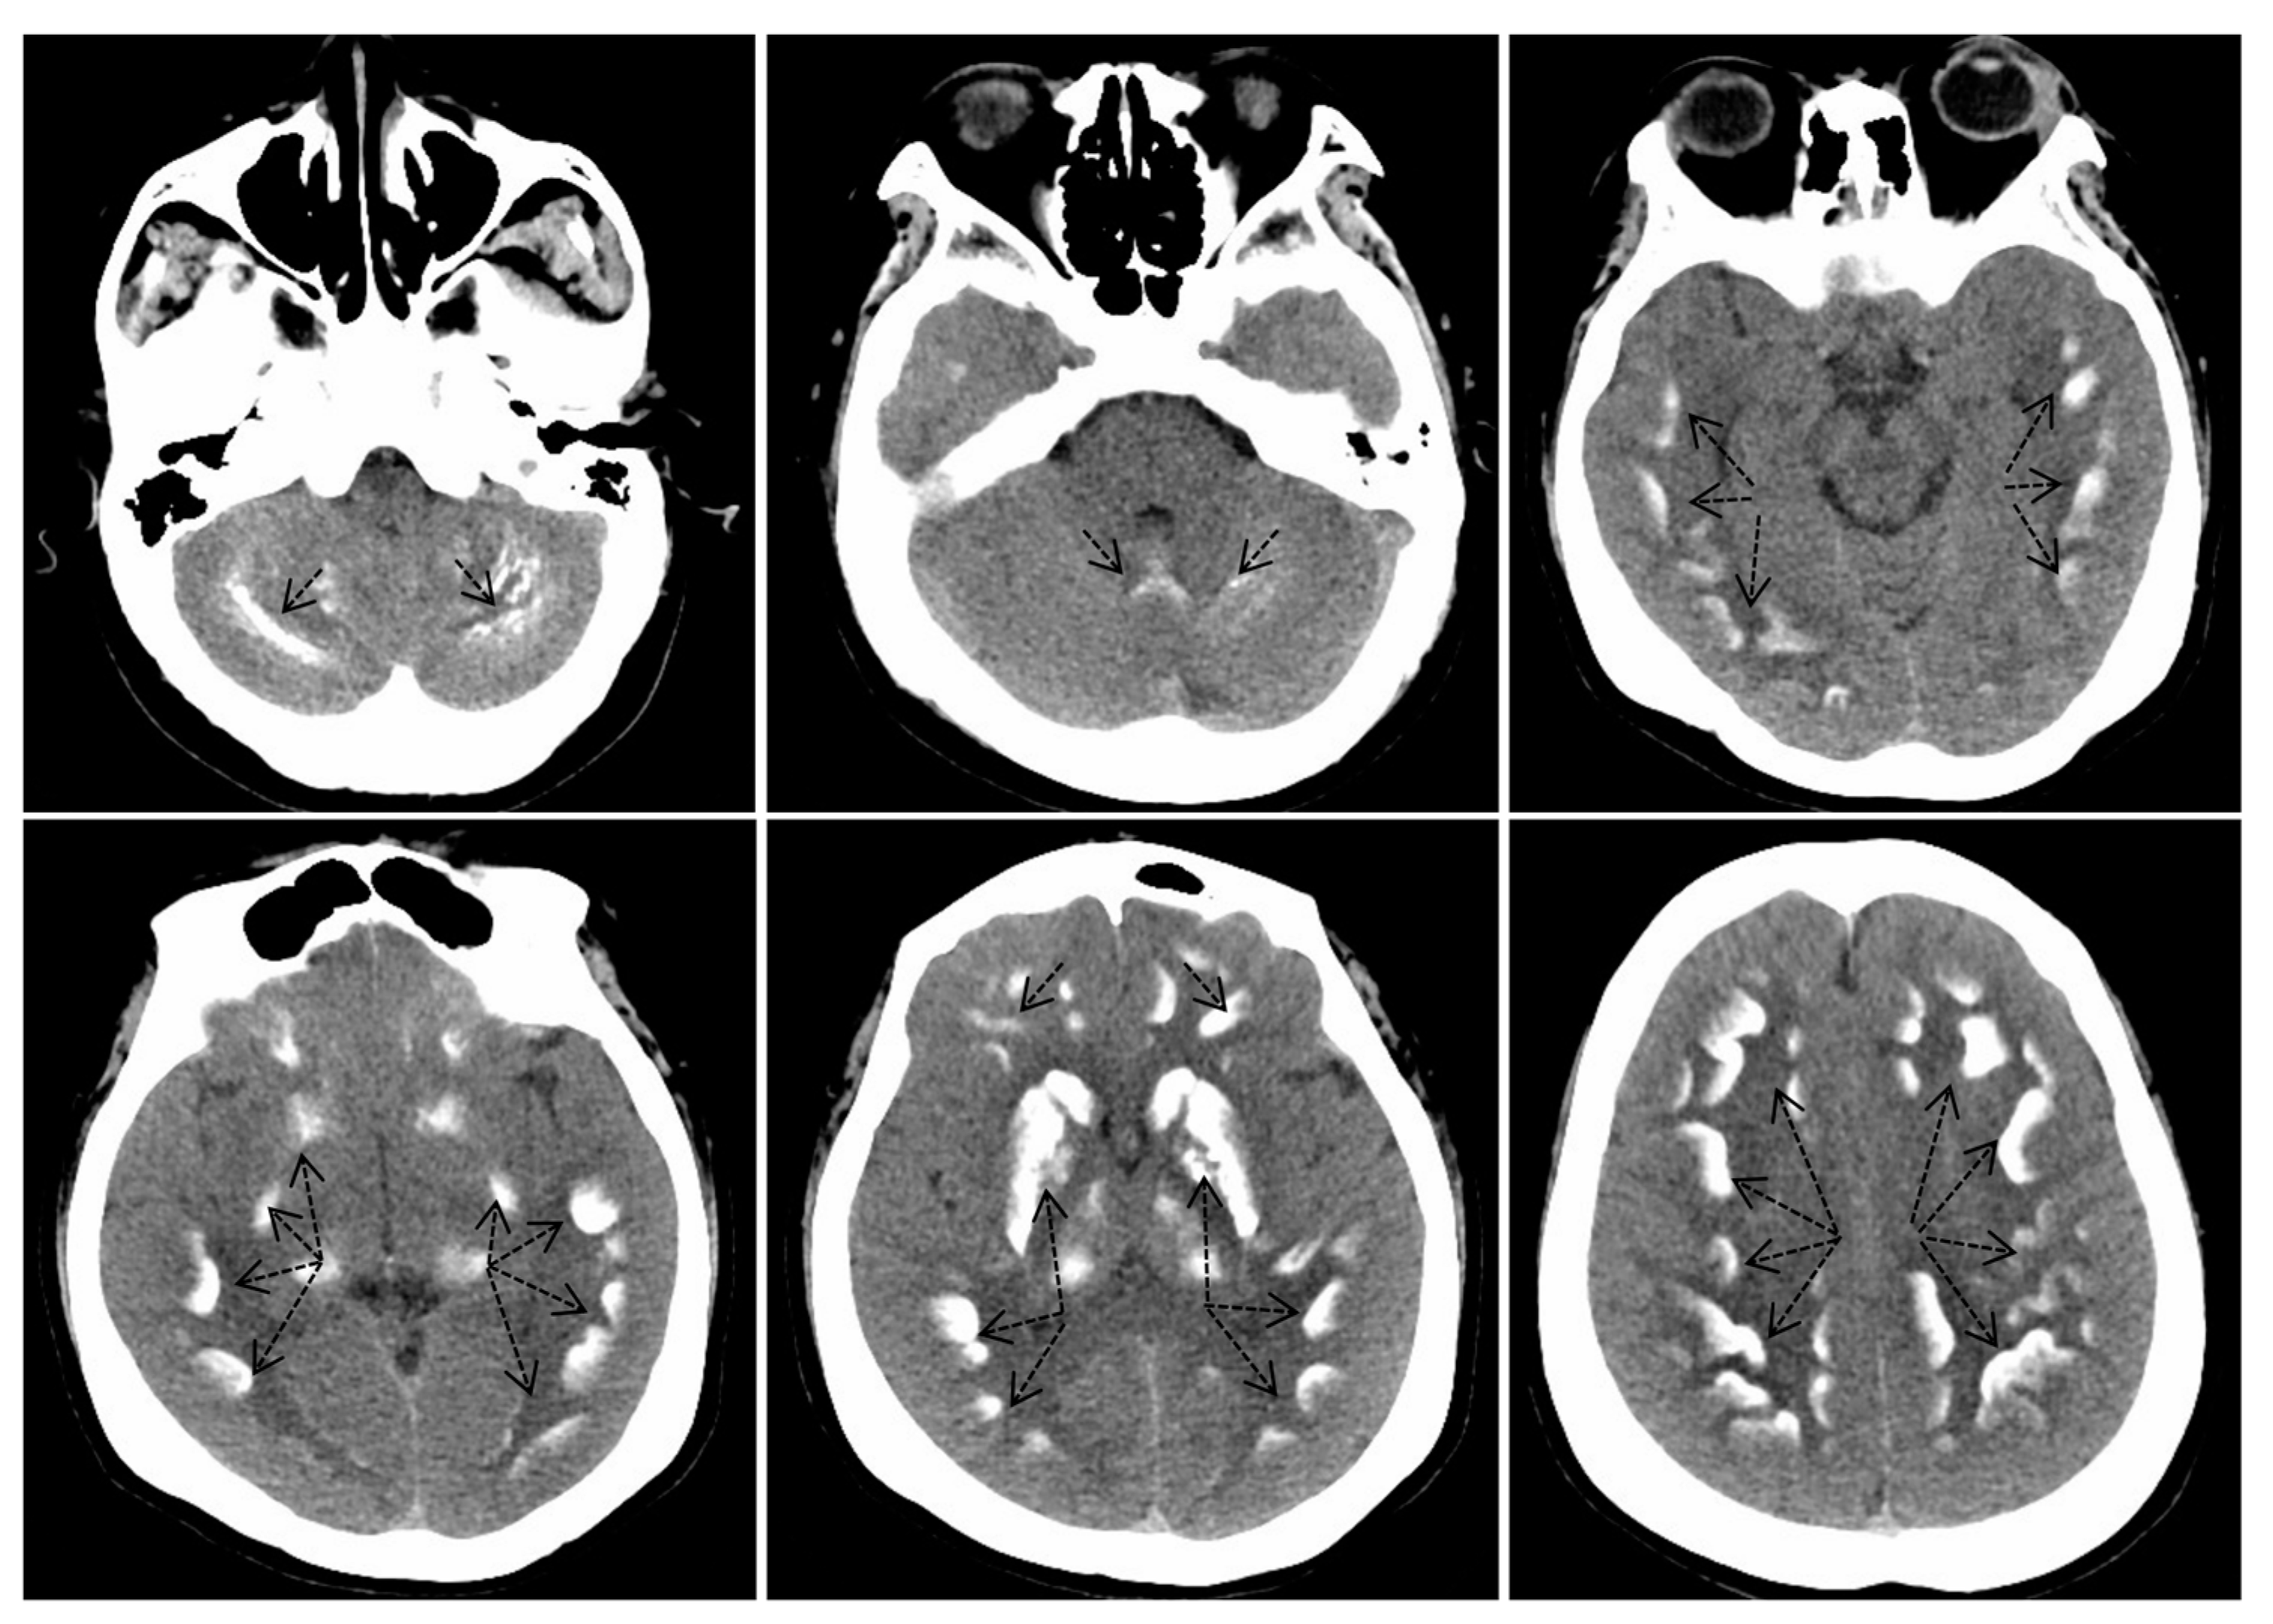

The laboratory biochemical analysis revealed that the proband’s calcium level was 1.63 mmol/L, her potassium level was 2.91 mmol/L, and her parathyroid hormone level was 412.7 ng/L, indicating a diagnosis of pseudohypoparathyroidism (Table 1). The CT scans demonstrated extensive bilateral calcifications in the basal ganglia, specifically involving the caudate nucleus, putamen, globus pallidus, thalamus, and dentate nucleus (Figure 2), which is characteristic of Fahr’s syndrome.

Figure 2.

Noncontrast computed tomography images of the head revealed calcifications in the bilateral basal ganglia, encompassing the caudate nucleus, putamen, globus pallidus, thalamus, and dentate nuclei. The black dashed arrows in the figure indicate areas of calcification.